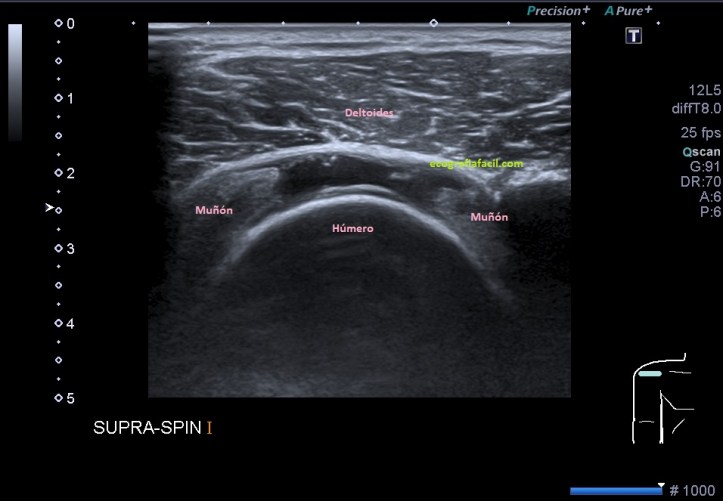

Si la rotura del tendón progresa pasamos a la fase final donde la rotura es importante, se llama rotura masiva y aquí la rotura es tan grande que el supraespinoso no se observa y vemos claramente el deltoides apoyando sobra la cabeza humeral. En este caso, el tendón no existe funcionalmente, pero debemos buscar los restos o cabos laterales que existen porque debemos medir la distancia entre ellos, con el objeto de que en algunos casos, la cirugía puede ser solución a esta patología, digamos, más grave dentro de los tres tipos de rotura que el tendón puede sufrir.

Si la rotura es reciente, líquido, si la rotura es antigua, simplemente veremos el músculo deltoides apoyar plácidamente sobre la cabeza del húmero, como en la imagen 4, donde ves los muñones laterales del tendón, inexistente y donde el deltoides ocupa su lugar apoyando en el hueso.